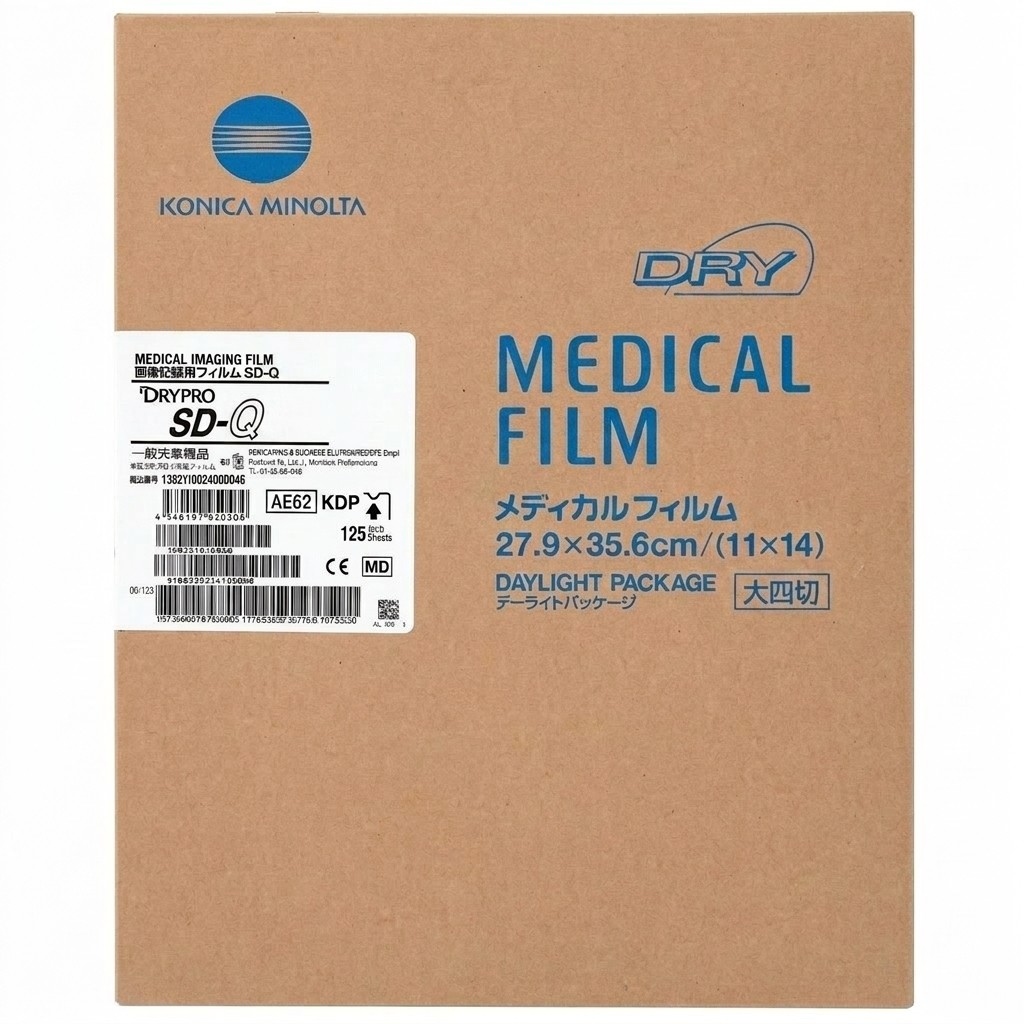

Products

We provide reliable service for our partners all around the globe. Offering well-known brands such as Fujifilm Healthcare, Carestream Health, Konica Minolta Healthcare and many others. Minimum order quantity is 1 pallet.